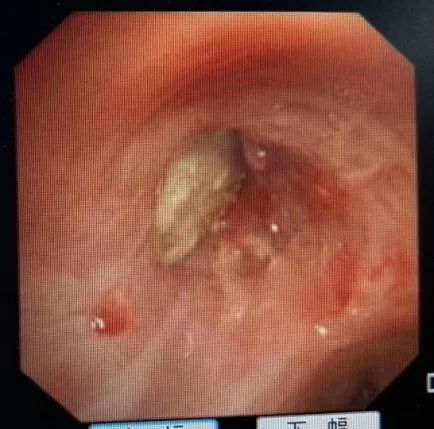

片刻,严主任已赶到并准备就位。只见镜头进入左总支气管,一只河虾的额刺赫然在目,完全阻塞了气管腔。所幸,额刺并没有扎入气管道引起大出血,不然后果不堪设想。

(镜头下的虾肉和取出后的虾)